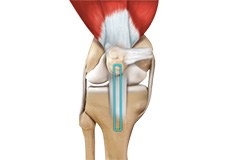

Tendons of the Knee

A tendon is a tissue that attaches a muscle to a bone. The quadriceps muscles of the knee meet just above the patella and attach to it through a tendon called the quadriceps tendon. The patella further attaches to the tibia through a tendon called the patella tendon. The quadriceps muscle, quadriceps tendon, and patellar tendon all work together to straighten the knee. Similarly, the hamstring muscles at the back of the leg are attached to the knee joint with the hamstring tendon.

Patellar Tendon Rupture

The patellar tendon works together with the quadriceps muscle and the quadriceps tendon to allow your knee to straighten out. Patella tendon rupture is the rupture of the tendon that connects the patella (kneecap) to the top portion of the tibia (shinbone).